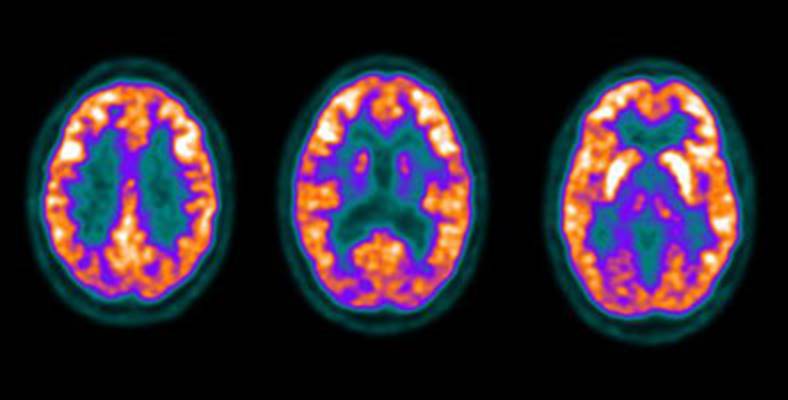

Figure 2 - Normal

brain activity: The image below demonstrates normal FDG brain activity.